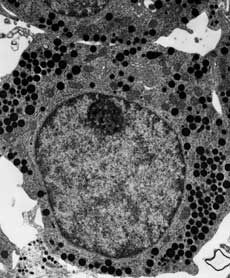

Electron microscopy (EM) is a technique for obtaining high resolution images of biological and non-biological specimens. It is used in biomedical research to investigate the detailed structure of tissues, cells, organelles and macromolecular complexes. The high resolution of EM images results from the use of electrons (which have very short wavelengths) as the source of illuminating radiation. Electron microscopy is used in conjunction with a variety of ancillary techniques (e.g. thin sectioning, immuno-labeling, negative staining) to answer specific questions. EM images provide key information on the structural basis of cell function and of cell disease.

There are two main types of electron microscope – the transmission EM (TEM) and the scanning EM (SEM). The transmission electron microscope is used to view thin specimens (tissue sections, molecules, etc) through which electrons can pass generating a projection image. The TEM is analogous in many ways to the conventional (compound) light microscope. TEM is used, among other things, to image the interior of cells (in thin sections), the structure of protein molecules (contrasted by metal shadowing), the organization of molecules in viruses and cytoskeletal filaments (prepared by the negative staining technique), and the arrangement of protein molecules in cell membranes (by freeze-fracture).